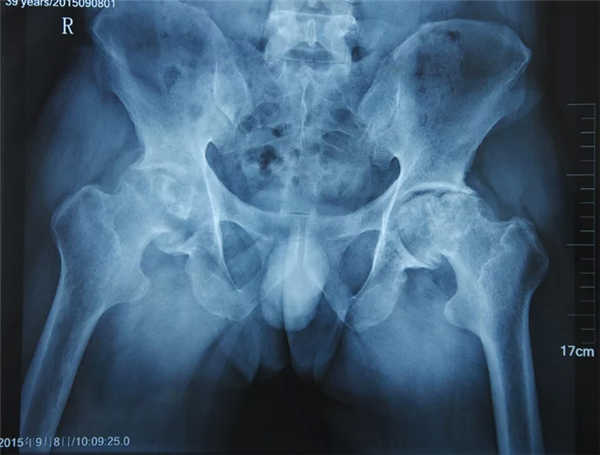

使用靶位体液渗透疗法治疗3个月:股骨头塌陷、骨缺损等问题得到一定缓解,病情好转

疼痛症状减轻,活动受限缓解